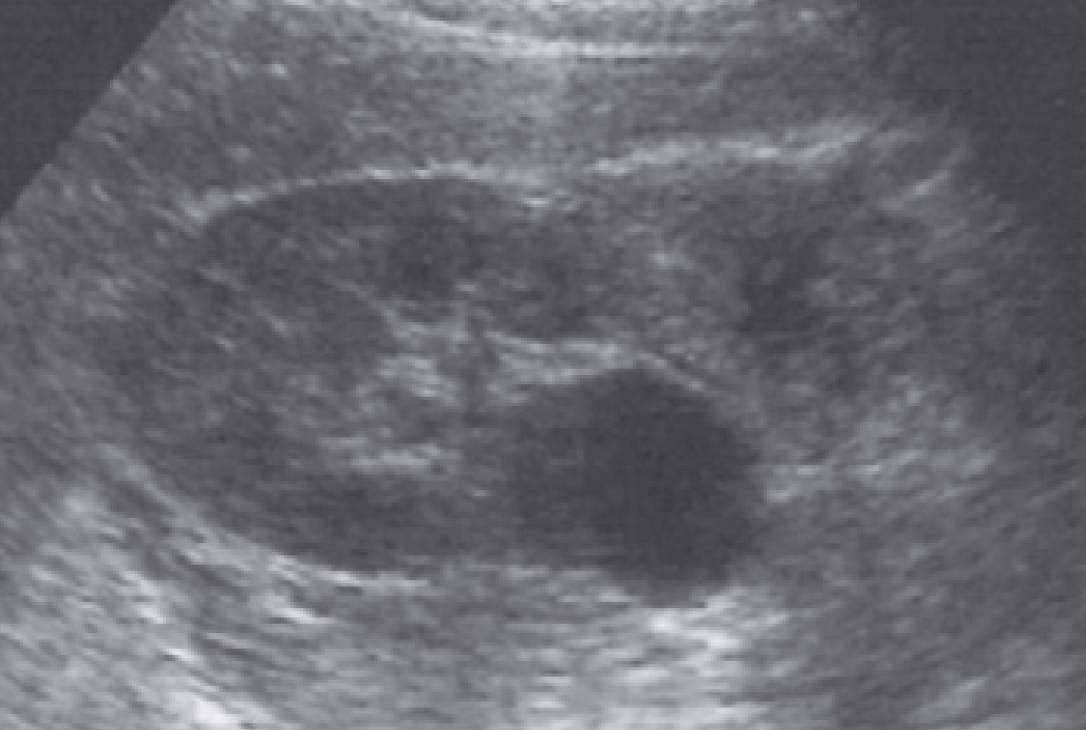

4-Extrarenal pelvis

هنا ببساطة يتواجد حوض الكلية خارج الكلية وكأنه كيس خارجي. الأهمية هنا تكمن في تمييزه بأنه تغير طبيعي وليس توسع في حوض الكلية أو كيس. التفرقة بينه وبين hydronephrosis تكون في عدم وحود توسع في calycis كما هو الحال في hydronephrosis.

في هذه الحالات يفضل التصوير بشكل transverse للتأكد.